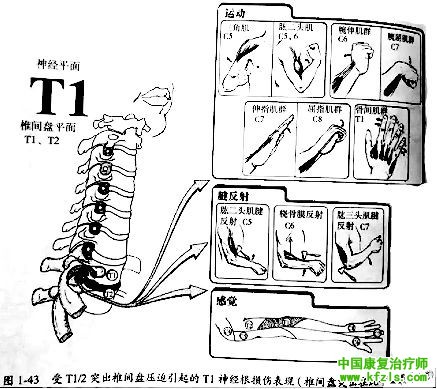

采用下述神经功能检査方法即可确定椎间盘突出的相应平面(图1-39至1-43)。

表1-1 归纳了颈椎各平面的神经功能检査方法, 同时也总结了其在颈髓病变尤其是颈椎间盘突出症中的临床应用。